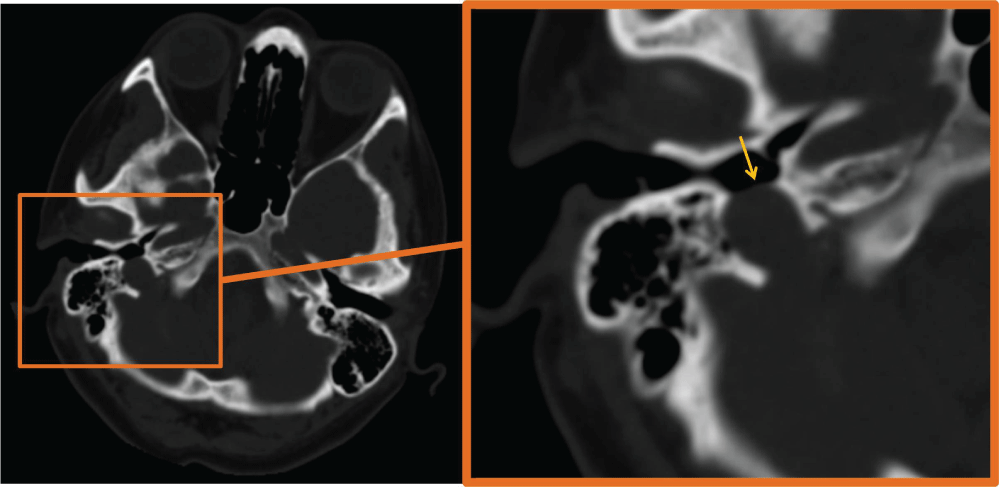

A 41-year-old female patient with 2-year history of tinnitus in right ear admitted to our clinic. The patient underwent temporal bone CT imaging. CT demonstrated right dehiscent high riding jugular bulb with absence of the right sigmoid plate (Figure 1).

Figure 1: CT demonstrates right dehiscent high riding jugular bulb with absence of the right sigmoid plate (arrow).

A dehiscent jugular bulb is defined as a normal venous variant with superior and lateral extension of the jugular bulb into the middle-ear cavity through a dehiscent sigmoid plate [1]. Despite its rare frequency, dehiscent jugular bulb is one of the common cause of pulsatile tinnitus. In a study, high resolution CT scans of 700 temporal bones of 350 patients were retrospectively examined for the incidence of vascular variations showed that dehiscent jugular bulb was seen in 27 (3.9%) temporal bones [2]. Patients with dehiscent jugular bulb can be completely asymptomatic or may suffer from dizziness, pulsatile tinnitus and hear loss [3]. Otoscopy may show a bluish, pulsatile mass. CT has a major role in outlining the defect of sigmoid plate [4]. During the middle ear surgery jugular bulb may injure; consequently, it is important to warn surgeons about this pitfall before the operation.